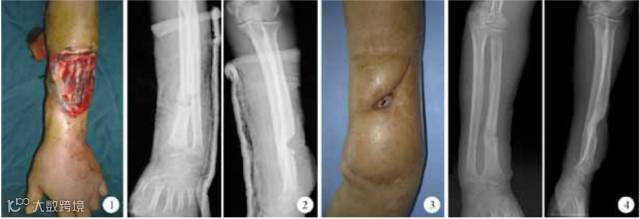

解放军第98医院烧伤整形科收治1例因机器轧烫伤致桡骨骨折、术后骨折感染外露、创面常规治疗不愈患者,采用脐带间充质干细胞局部移植治疗4次后,创面肉芽组织迅速增生、填满窦道并上皮化,12天后创面愈合。x线片检查示治疗后骨折端骨痂开始大量生长、骨折线渐模糊。伤后1年患者入院行皮瓣修薄术,见局部皮肤无溃破,骨折愈合并重塑。

图1. 治疗前伸肌群毁损伴桡骨骨折

图2. 伤口6个月X线片示骨折端杯状骨缺损,未见骨痂生长

图3. 伤口6个月骨折端外露窦道

图4. 伤口1年后正侧位X线片示桡骨骨折愈合并重塑